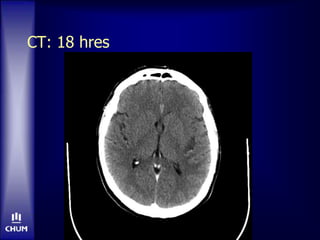

M. N.  Hommede 62 ans, droitier • DLP • Db2 de novo  AVC ACM gauche • Déficit fluctuant; NIHSS 16  10 • Famille indécise re. tPA  CT…

M. N.  tPA-IV •OTTT: 3h15  Hyperglycémie malgré insuline IV  Aucune amélioration clinique

CT: 18 hres